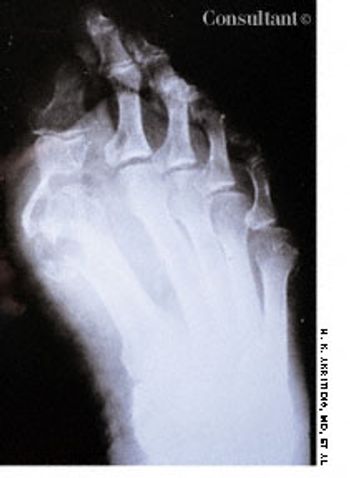

A 73-year-old man was admitted to the hospital with pain in his hands, feet, and elbows. The patient, an alcoholic, had a 20-year history of hypertension and diabetes. Deformities of the hands and feet had developed during the past 5 years. Tophi were present over both ear lobes. The serum uric acid level was 15 mg/dL.